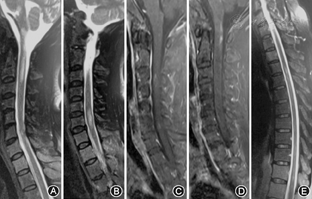

患者女性,50岁,因"发热、恶心呕吐10 d,左侧耳周疼痛7 d"于2016年1月7日收入我院。患者10 d前无明显诱因下出现发热,体温38.5 ℃,数小时后出现频繁恶心呕吐,当天入住当地县人民医院,予以更昔洛韦抗病毒及对症支持治疗,第2天患者体温恢复正常,但恶心呕吐症状持续无好转。7 d前开始出现左侧耳周阵发性针刺样疼痛,伴有烧灼感。当地医院血常规、超敏C反应蛋白、红细胞沉降率、降钙素原、肺部CT、头颅MRI检查等未见明显异常。1月6日行腰椎穿刺检查:压力110 mmH2O(1 mmH2O=0.009 8 kPa),潘氏试验阴性,脑脊液蛋白255 mg/L,白细胞计数19×106 μl,淋巴细胞百分比95%。经治疗后患者仍有恶心呕吐、左侧耳周疼痛,家属要求转来我院进一步治疗,当地医院出院诊断为"病毒性脑膜炎" 。入院体检:体温36.3 ℃,血压133/85 mmHg(1 mmHg=0.133 kPa),全身未见皮疹,意识清楚,双眼视力正常,两侧瞳孔等大,对光反射存在,口齿清楚,伸舌居中,颈软,四肢肌力、肌张力正常,四肢腱反射(++),左侧面部周边及耳廓区域痛觉减退,感觉障碍呈洋葱皮样分布,两侧巴宾斯基征阴性,心肺听诊正常。既往体健,否认烟酒嗜好,否认家族遗传性疾病及传染病史。入院诊断:继发性三叉神经痛原因待查。入院后查血常规、尿常规、肝肾功能、红细胞沉降率、超敏C反应蛋白、TORCH检查、EB抗体、单纯疱疹病毒抗体、柯萨奇病毒抗体、甲状腺功能常规、甲状腺球蛋白抗体、甲状腺过氧化物酶、肿瘤标志物、自身抗体谱、血管炎抗体、抗核抗体等未见明显异常。脑干听觉诱发电位、视觉诱发电位未见明显异常。头颅增强MRI(1月10日)未见明显异常。予以更昔洛韦抗病毒,加巴喷丁胶囊抑制疼痛及对症支持治疗。患者病情仍有进展,1月11日出现左上肢阵发性疼痛伴痛觉减退,1月12日出现尿潴留、便秘,提示脊髓损害,予以完善颈、胸髓磁共振检查。患者行颈髓MRI(1月12日)示:脑干、颈2、颈6椎体水平炎性病变(图1A、图1B);颈髓增强MRI(1月15日)示:脑干、颈1~4及颈6~7椎间盘水平异常强化病灶(图1C、图1D);胸髓MRI(1月16日)示:胸4~5及胸11椎体水平炎性病变(图1E)。1月18日患者出现左下肢阵发性强直性痉挛,疼痛剧烈,加巴喷丁胶囊逐渐加量。1月19日再次行腰椎穿刺检查:压力75 mmH2O,潘氏试验弱阳性,脑脊液蛋白495 mg/L,白细胞计数53×106 μl,淋巴细胞百分比100%。血清及脑脊液送检返回结果(2016年1月21日,康圣环球医学检验公司,ELISA法,编号B62002900505)示脑脊液AQP4-IgG(++),血清AQP4-IgG(+);脑脊液寡克隆区带试验阴性。最后诊断为NMOSD,停用更昔洛韦,予以甲泼尼龙(每天800 mg ,每3天减半),丙种球蛋白(每天20 g,每日1次×5 d),辅以护胃、补钾、补钙等对症治疗。免疫治疗第3天,患者恶心呕吐症状消失,随后几天耳周疼痛、左上肢阵发性疼痛好转。患者左下肢阵发性强直性痉挛,疼痛难忍,使用加巴喷丁(每次600 mg,每天4次)治疗1周后仍难以控制,2月1日改用卡马西平(每次100 mg,每天2次),2月2日症状得到控制。随后,激素逐渐减量至泼尼松15 mg/d口服,联合硫唑嘌呤100 mg/d口服。患者病情好转出院,门诊随访,大小便功能亦逐渐好转。

顽固性恶心呕吐是NMOSD患者脑干受损的最常见症状,与致病性AQP4-IgG引起中脑导水管周围或延髓背内侧结构的孤束核和菱形区域受损有关,这些部位均是AQP4高表达区域[5,11]。该患者颈髓MRI检查证实延髓存在炎性病灶,临床症状与影像特征对应存在,支持NMOSD的诊断。Kremer等[12]研究表明,NMO患者中31.4%存在脑干受损症状,其中三叉神经痛的发生率为2.5%。该患者出现左侧耳周阵发性针刺样疼痛及烧灼感,体检发现左侧面部周边及耳廓区域痛觉减退,感觉障碍呈洋葱皮样分布,诊断继发性三叉神经痛。患者颈髓MRI显示高位颈髓炎性病灶累及三叉神经脊束核下部,从而导致继发性三叉神经痛,临床症状与影像特征一致。随着病情进展,患者出现左侧上肢疼痛,左上肢腱反射减弱,大小便功能障碍,肢体阵发性强直性痉挛,提示病情进一步进展,病灶从脑干向下延伸到脊髓,脊髓MRI检查结果证实病灶从脑干延伸到了脊髓。患者肢体阵发性强直性痉挛发作频繁,疼痛难忍,加巴喷丁逐渐加量至2 400 mg/d,仍难以控制,改用卡马西平200 mg/d,次日患者症状明显好转,提示对卡马西平非常敏感。Kim等[13]的研究中发现,这种卡马西平敏感性肢体阵发性强直性痉挛在NMOSD中比多发性硬化更常见。